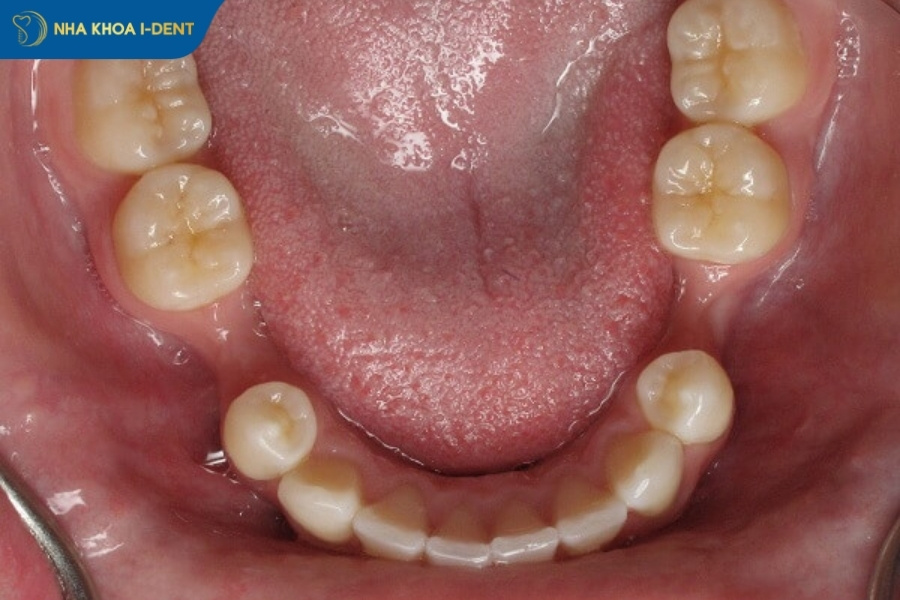

- Về mặt cấu trúc dài hạn, việc nhổ răng có thể khiến các răng bên cạnh có xu hướng dịch chuyển vào khoảng trống, gây lệch khớp cắn. Ngoài ra, việc nhổ răng lâu không trồng lại sớm gây tiêu xương hàm làm má hóp.

Lệch khớp cắn là biến chứng dài hạn xảy ra khi các răng bên cạnh và răng đối diện với vị trí răng đã nhổ bắt đầu dịch chuyển vào khoảng trống, làm thay đổi khớp cắn tự nhiên. Quá trình này diễn ra từ từ trong vòng 6-18 tháng sau khi nhổ răng và có thể gây ra nhiều hậu quả nghiêm trọng nếu không được can thiệp kịp thời.

Tiêu xương hàm là quá trình mất xương tự nhiên và không thể đảo ngược sau khi nhổ răng, là hậu quả của mất răng dài hạn nghiêm trọng. Trong điều kiện bình thường, lực nhai từ răng kích thích xương hàm tái tạo liên tục. Khi răng bị nhổ, lực này biến mất, xương không còn được kích thích và bắt đầu tiêu biến. Quá trình này diễn ra chủ yếu ở bề mặt ngoài xương (80-90%), làm giảm chiều rộng và chiều cao của xương ổ răng.

Hậu quả tiêu xương hàm bao gồm thay đổi hình dạng khuôn mặt – má và môi xẹp xuống, mất thẩm mỹ, khó khăn khi làm implant sau này do thiếu xương, răng giả không khớp tốt và dễ lung lay, tăng nguy cơ gãy xương hàm ở người cao tuổi.